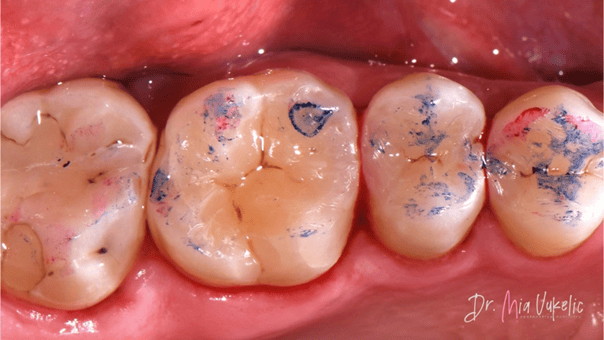

La paciente acudió a la clínica para un chequeo anual. Tras un examen clínico y radiográfico, se diagnosticó una lesión de caries secundaria en la superficie oclusal del diente 26, así como dos lesiones cariosas adicionales en las superficies distales de los dientes 24 y 25. La paciente no refirió síntomas específicos. El tratamiento indicado consiste en la colocación de una restauración Clase I en el diente 26 y restauraciones Clase II en los dientes 24 y 25.

El material utilizado para la restauración fue la resina Transcend™ (Ultradent Products). La pared proximal se realizó con el tono EW, mientras que las dos capas horizontales posteriores se colocaron en tono A3D. Las características secundarias se lograron utilizando el modificador de color Kolor + Plus™ en tono café (Kerr*).

Como puede observarse en las imágenes finales, la resina Transcend™ ofrece una apariencia estética excepcional para la restauración. El sistema de matrices seccionales Halo permitió lograr una excelente anatomía proximal, tal como se aprecia en la radiografía.